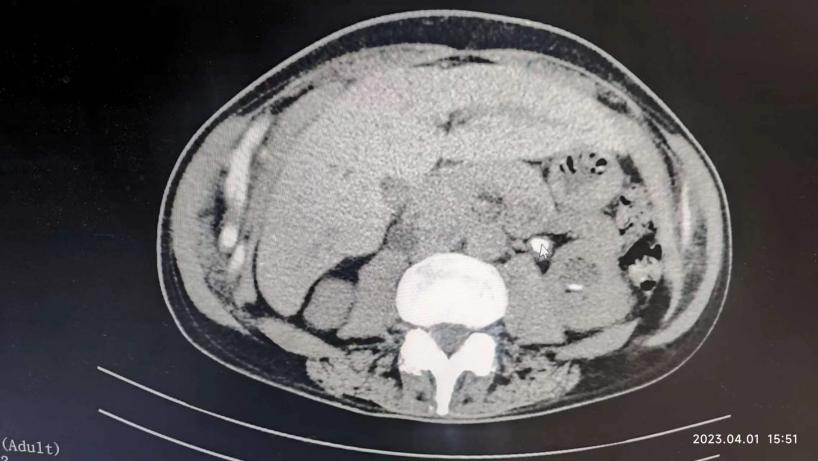

原来冉先生曾在六年前也患过一次肾结石,由于他从小患有强直性脊柱炎,脊柱生理结构与普通人不同,手术难度、麻醉难度与普通结石患者完全不在同一个级别上。当时他辗转找到刘主任,为他成功完成了微创碎石手术。

六年后,冉先生再次患者上双肾结石+左侧输尿管结石,他毫不犹豫地再次找到刘洪春主任。在刘洪春主任带领的泌尿外科团队的精心安排下,制定了“输尿管软镜+摩西钬激光碎石术”两期手术的方案,采用局部麻醉方式分期进行。